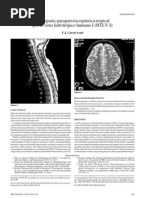

La gammagrafa isotpica lizar las partes blandas, sin e m b a r g o , a nivel seo es una tcnica sensi-

es u n a tcnica m u y sensi- ble, p e ro c o n m e n o r e s p e c i f i c i d a d q u e la TC. La tcnica p e r m i t e valorar

ble, y a q u e detecta las a l t e - la afectacin m e d u l a r en la patologa c o m p r e s i v a del raquis (hernia de

raciones f u n c i o n a l e s antes disco, canal m e d u l a r estrecho), la valoracin d e las estructuras intraarti-

de q u e aparezca u n a lesin culares d e la r o d i l l a (patologa del m e n i s c o y d e ligamentos).

estructural. Sin e m b a r g o , es

p o c o especfica al n o tratar-

Q RECUERDA

se d e u n a tcnica morfol-

La r e s o n a n c i a magntica es d e e l e c c i n para el diagnstico d e la p,

gica. El istopo ms f r e - logia del raquis.

c u e n t e m e n t e e m p l e a d o son

los c o m p u e s t o s d e tecne-

c i o . El g a l i o (Ga-67) es til A s i m i s m o , es valiosa para el diagnstico de la sinovitis v i l l o n o d u l a r

para i d e n t i f i c a r las i n f e c c i o - p i g m e n t a d a y e n la patologa m u s c u l a r i n f l a m a t o r i a (Tabla 4 ) .

nes y los procesos neoplsi-

cos, ya q u e es e n estos t e j i -

T R A T A M I E N T O EN R E U M A T O L O G A

dos e n los q u e se l o c a l i z a

(Figura 4 ) . Sntomas leves Sntomas graves

Figura 4. C o r t e sagital m o s t r a n d o vrtebra c i d a d d e los c o m p u e s t o s d e

angiomatosa y siringomielia t e c n e c i o en las i n f e c c i o n e s